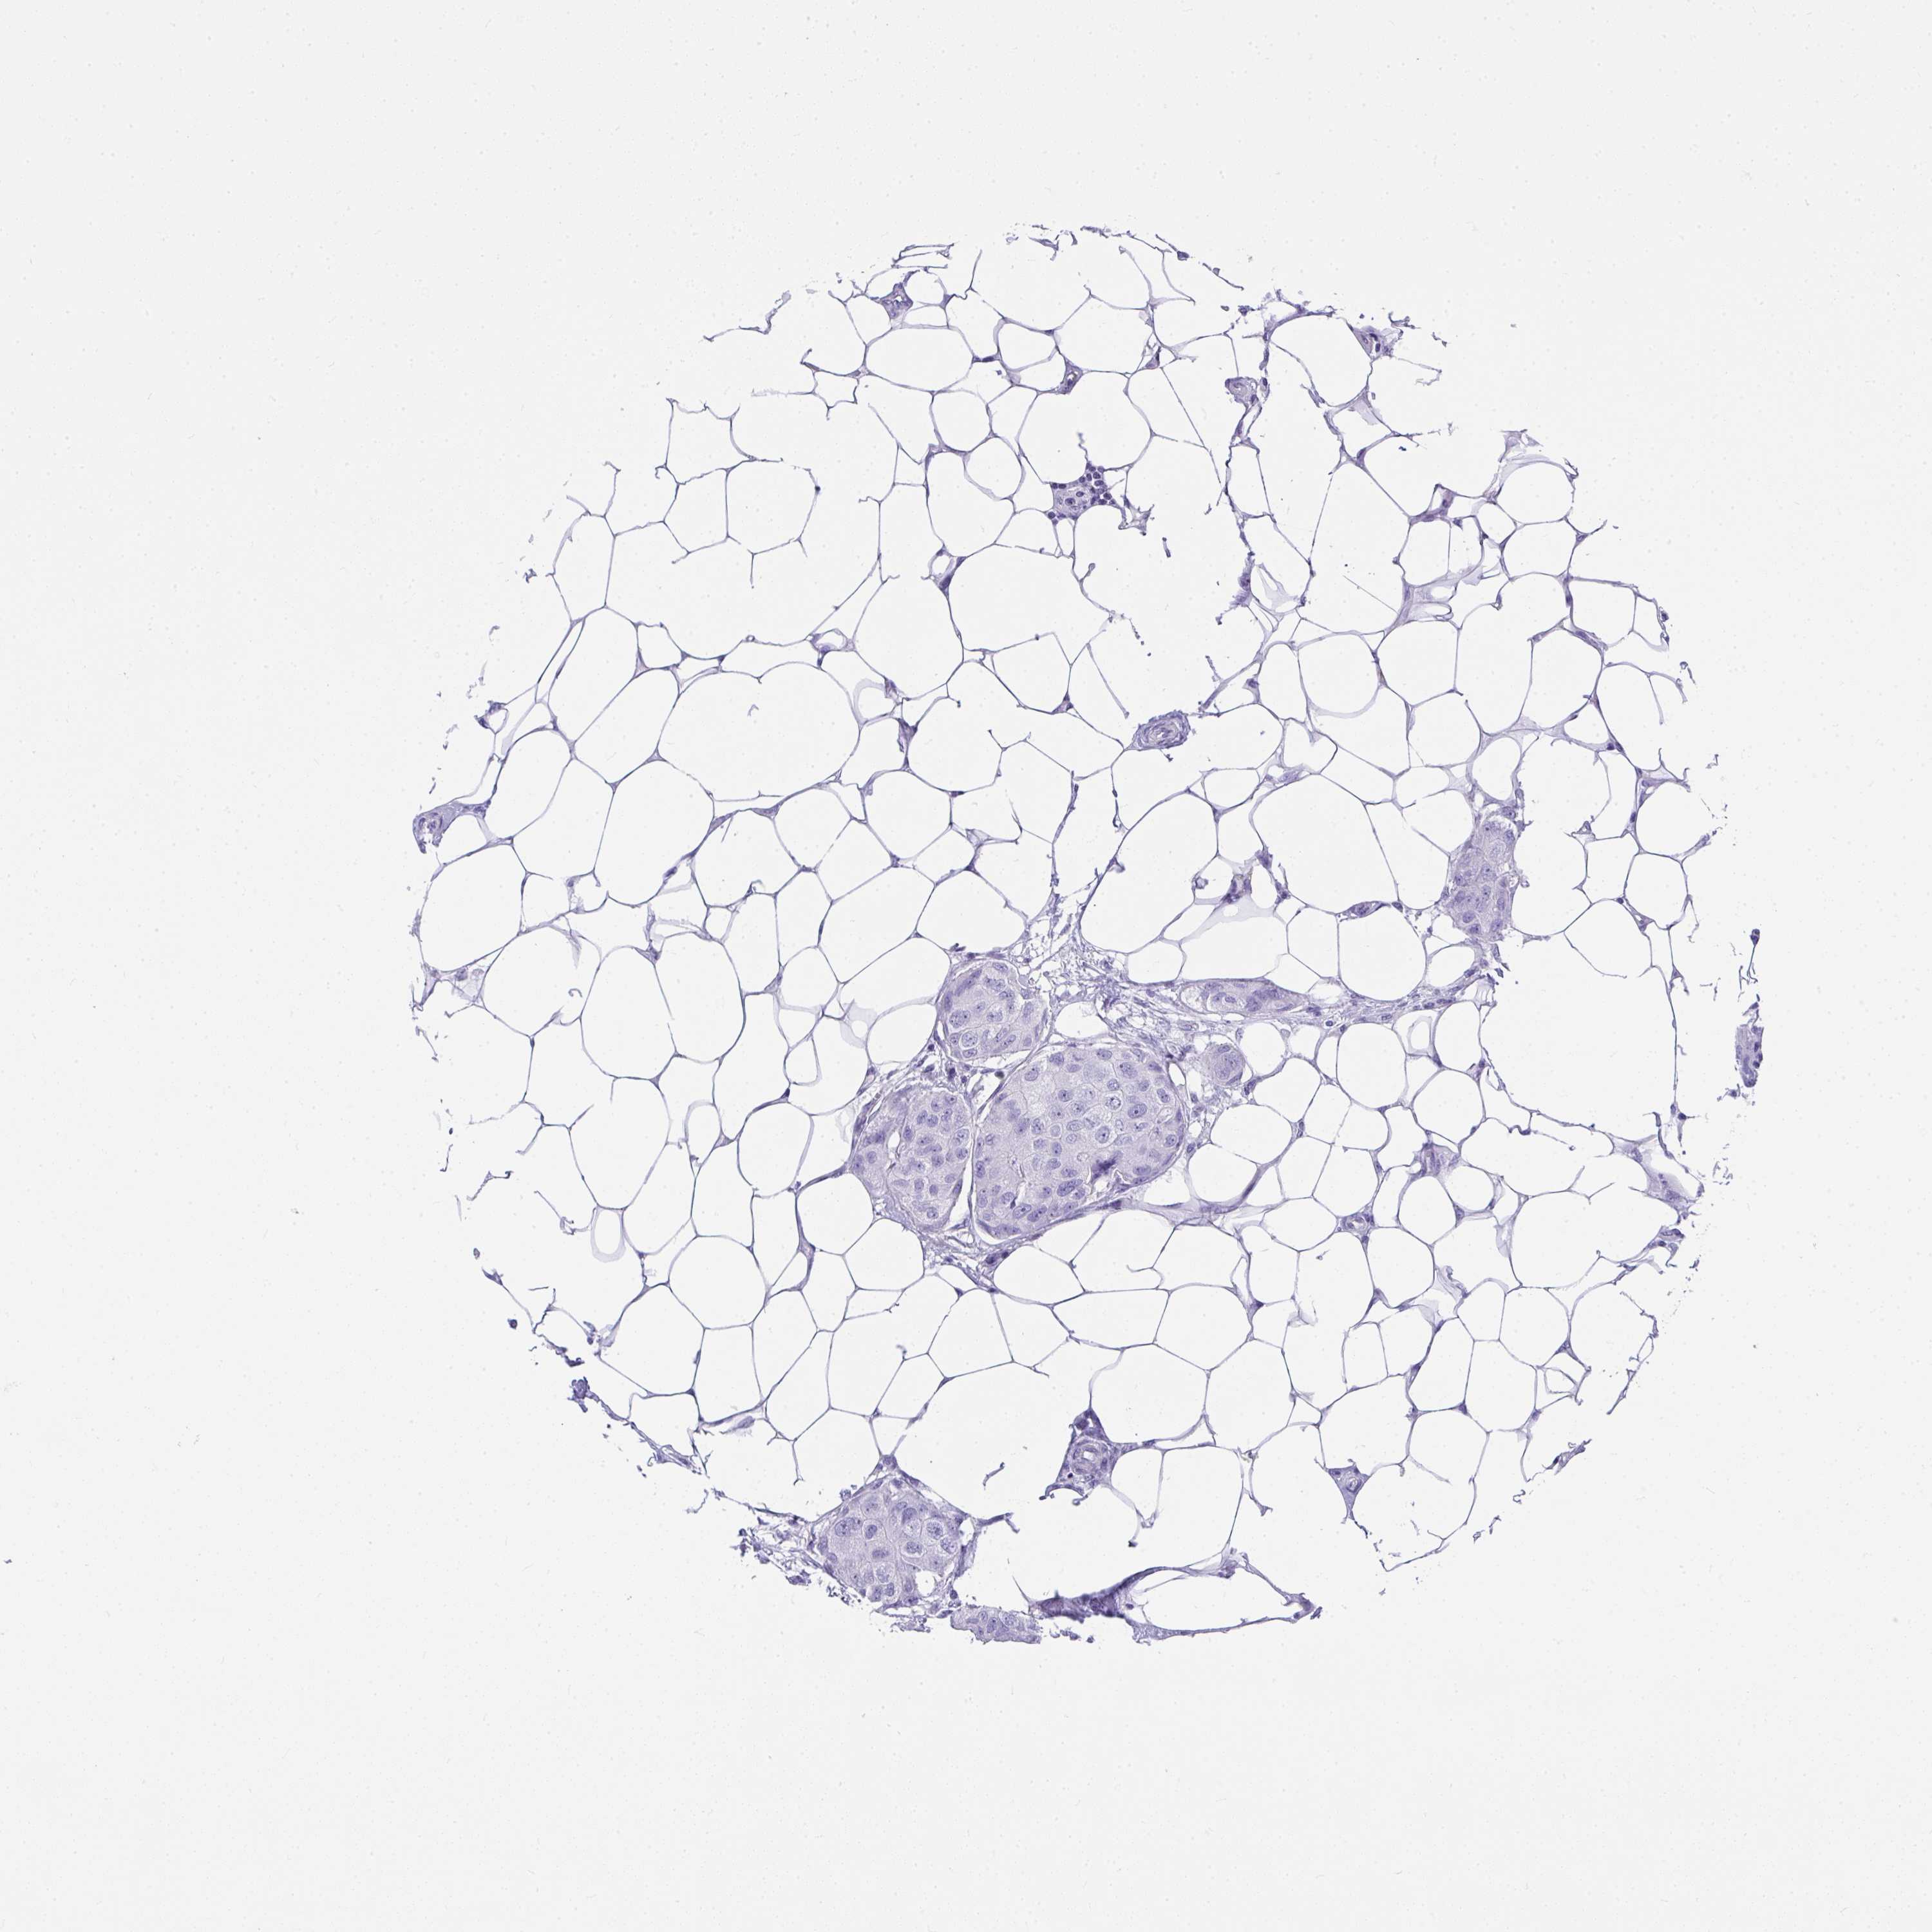

Breast cancer

Human cancer